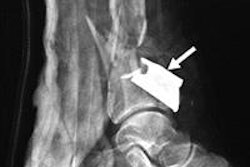

“Imaging is pivotal. Many of these patients undergo multiple different scans,” Rahmatullah told AuntMinnie.com. “CT is the best method to check for any abdominal penetrations, especially when it comes to shrapnel and shrapnel-related injuries.”

Bombings that involve explosives packed with metal fragments can alter the patterns and severity of injuries. This means imaging is necessary to determine treatment strategies, though MRI’s use is limited in these cases. Rahmatullah said that patients are referred for advanced care if smaller healthcare facilities do not have the equipment or personnel to manage these events.

CT exams made up the most common imaging method at 42% on first investigation, with ultrasound being next at 35%. Digital x-ray, meanwhile, was third at 17%. Fluoroscopy, angiography, and nuclear scans all came in at less than 5%.